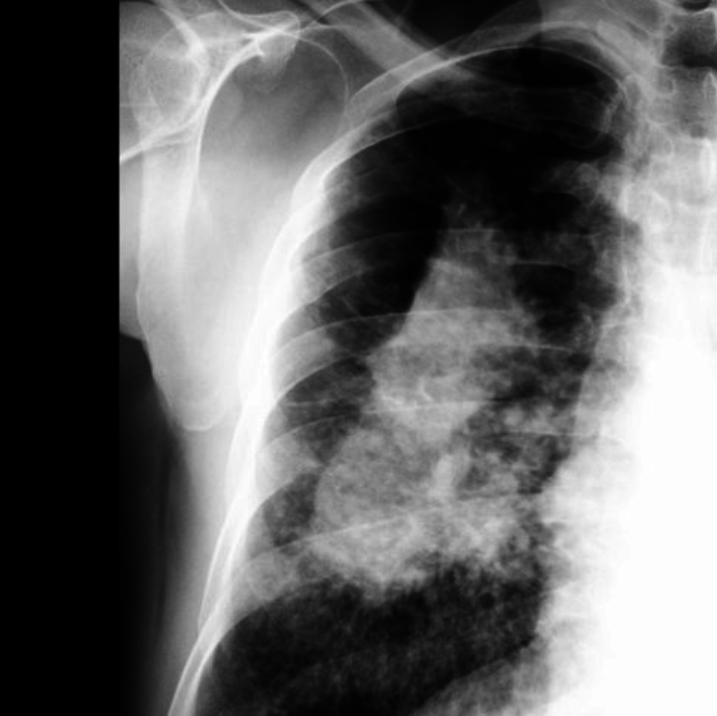

Accompanied by a cough and a progressive shortening of breath, the severe stage of the disease is extremely painful and will cause patients to gasp for air. The tiny particles of silica dust lodge in the lungs and generate scar tissue, which reduces the capacity to receive oxygen.